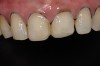

Fig 11. Postoperative frontal smile view.

Figure 11

A few weeks later, the facial veneers were bonded directly to the underlying enamel. A postoperative photograph (Figure 11) revealed the restored harmony of the patient’s smile and the occlusal contacts in MIP (Figure 12). The palatal surfaces restored with nanofilled composite resin developed good anterior guidance that was harmonized to the patient’s chewing cycle (Figure 13 and Figure 14).19